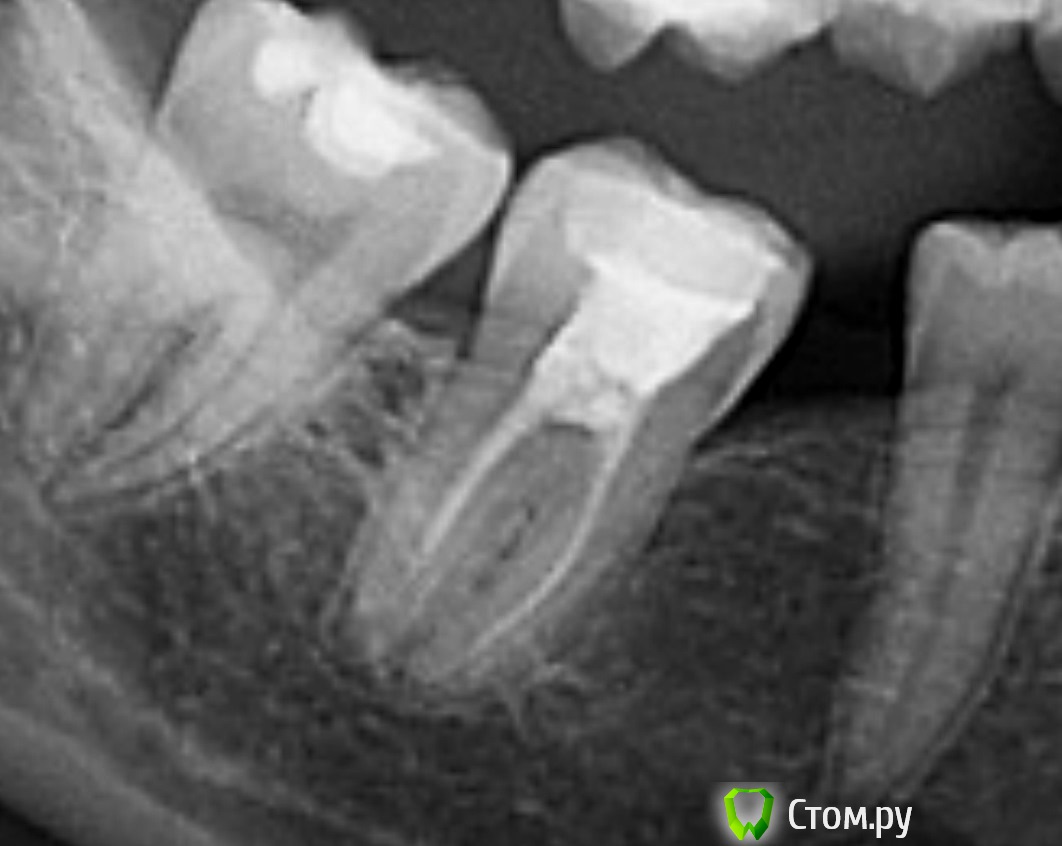

dr-krasnov Опубликовано 25 июня, 2014 Поделиться Опубликовано 25 июня, 2014 (изменено) Сделал покрупнее, в 1 квадранте есть сомнительный участок, выделил красным, по 36 и 37, много раз видел как в подобных ситтуациях зубы перелечивались. Это сложно, требует высокой квалификации эндодонтиста и наличия микроскопа. При любом варианте лечения, Вам показано КЛКТ челюстно-лицевой области. А ну и есть лишние 8 ки. http://s019.radikal.ru/i637/1406/7e/0388738e7075.jpg Изменено 25 июня, 2014 пользователем dr-krasnov Ссылка на комментарий

Bier Опубликовано 25 июня, 2014 Поделиться Опубликовано 25 июня, 2014 наверху проблемы у 16з 100% есть. Зубы можно перелечить с большой вероятностью успеха. В умелых руках конечно. Ссылка на комментарий

art700 Опубликовано 25 июня, 2014 Поделиться Опубликовано 25 июня, 2014 По-мойму проблема в 16, кт, либо прицельный для начала бы сделать Ссылка на комментарий

Korel Опубликовано 26 июня, 2014 Поделиться Опубликовано 26 июня, 2014 При удалении какой должен быть микроскоп? Никакой. Другой вопрос, мож. ещё рано удалять. КЛКТ мне не назначили, возможно ли лечение без него? Да. но значит. удобнее и информативнее с ним т.к. можно "повертеть" Ваши зубки со всех сторон и рассмотреть каждый мм. А что сомнительного в участоке в 1 квадранте? http://s006.radikal.ru/i214/1406/3b/b9dc1a606cb6.jpg 16 нужд. в перелечке, которой можно заняться после решения проблем с 36-37 Почему 8 ки лишние? Пока с этим можно не заморачиваться , и решать этот вопрос после решения вопросов с 36-37 и 16 Можно ли подождать с лечением 3 недели? Свищи появились постепенно...около 6 месяцев...думала, что они пройдут, Ничего не напоминает? По этому вопросу надо смотреть ОЧНО. Ссылка на комментарий

DokDent Опубликовано 26 июня, 2014 Поделиться Опубликовано 26 июня, 2014 а 4.7 тоже хочет перелечиться 1 Ссылка на комментарий